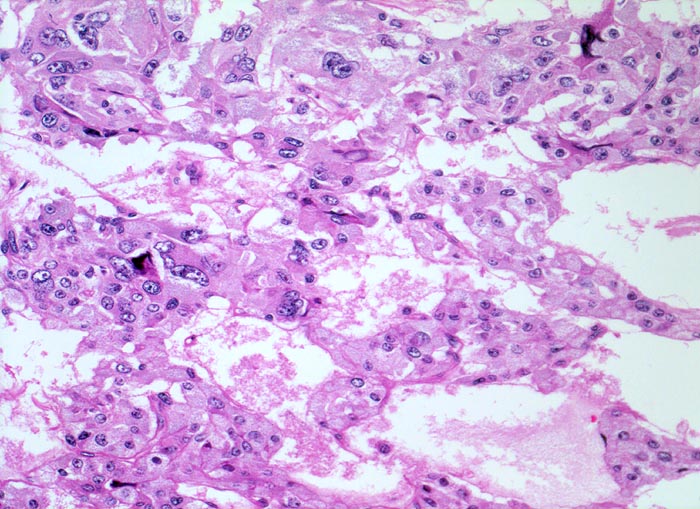

Phaeochromozytom

«Zellballen» aus teils spindelig konfigurierten, grossen Tumorzellen. In den Bindegewebssepten um die Zellballen lassen sich zahlreiche dilatierte Blutgefässe nachweisen.

Der Patient klagt über rezidivierende Kopfschmerzen seit zirka zwei Monaten. In letzter Zeit hat er Alcacyl genommen, jedoch ohne Erfolg. Die Computertomographie des Abdomens zeigt einen 5cm grossen Tumor im Bereich der rechten Nebenniere. Die Familienanamnese für multiple endokrine Neoplasien (MEN) ist bland.